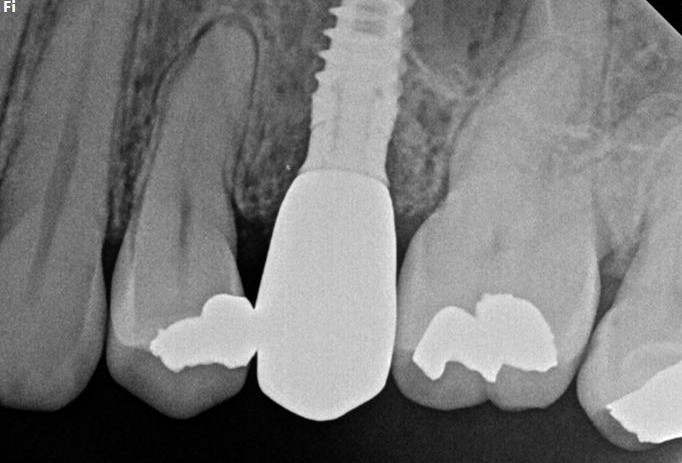

INITIAL STATE

Clinical and radiographic examination revealed a failed implant with signs of periimplant tissue compromise. Intraoral evaluation demonstrated inadequate soft tissue quality and unfavourable conditions for immediate restoration. CBCT imaging was performed to assess bone volume, implant position, and anatomical limitations prior to treatment planning.